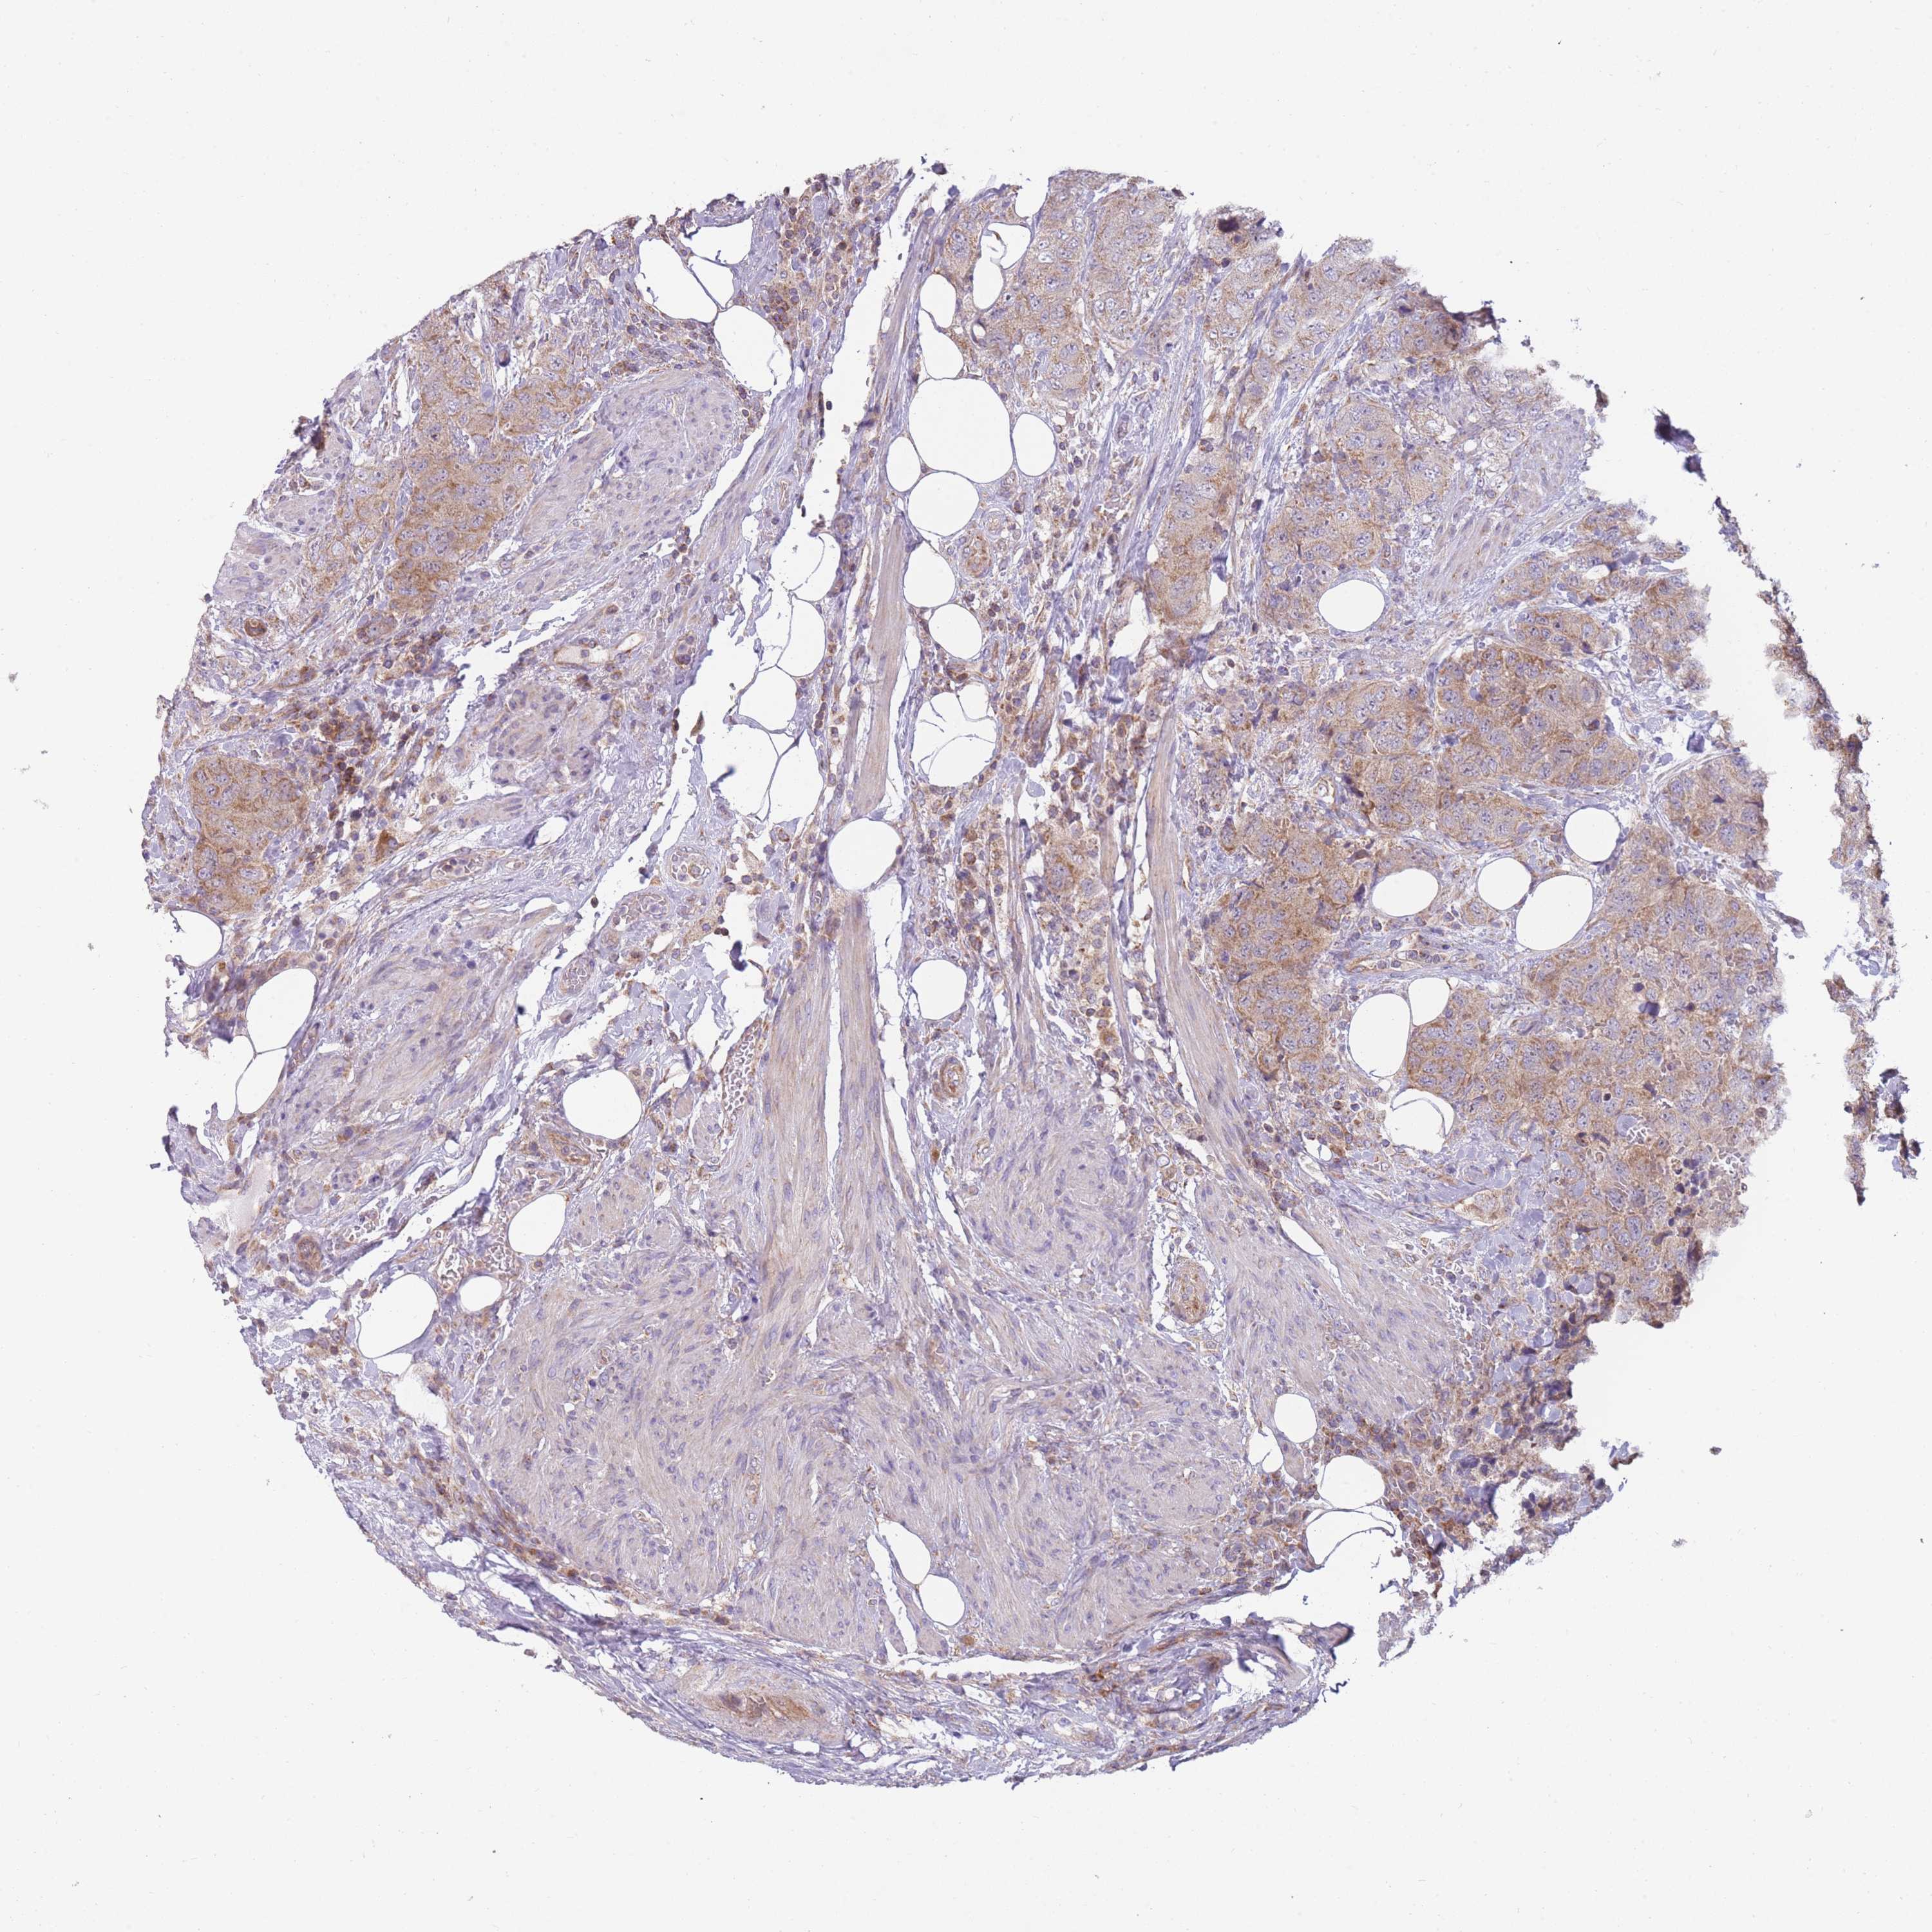

UROTHELIAL CANCER - Protein expressioni

A mouse-over function shows sample information and annotation data. Click on an image to view it in a full screen mode. Samples can be filtered based on level of antibody staining by selecting one or several of the following categories: high, medium, low and not detected. The assay and annotation is described here.

Note that samples used for immunohistochemistry by the Human Protein Atlas do not correspond to samples in the TCGA dataset.

Antibody stainingi

Antibody staining in the annotated cell types in the current human tissue is reported as not detected, low, medium, or high, based on conventional immunohistochemistry profiling in selected tissues. This score is based on the combination of the staining intensity and fraction of stained cells.

Each image is clickable and will lead to virtual microscopy that enables deeper exploration of all samples and also displays staining intensity scores, fraction scores and subcellular localization as well as patient and tissue information for each sample.

Antibody HPA042268

Staining

High

Medium

Low

Not detected

Intensity

Strong

Moderate

Weak

Negative

Quantity

>75%

75%-25%

<25%

None

Location

Urothelial carcinoma, High grade

Urothelial carcinoma, NOS

Urothelial carcinoma, Low grade